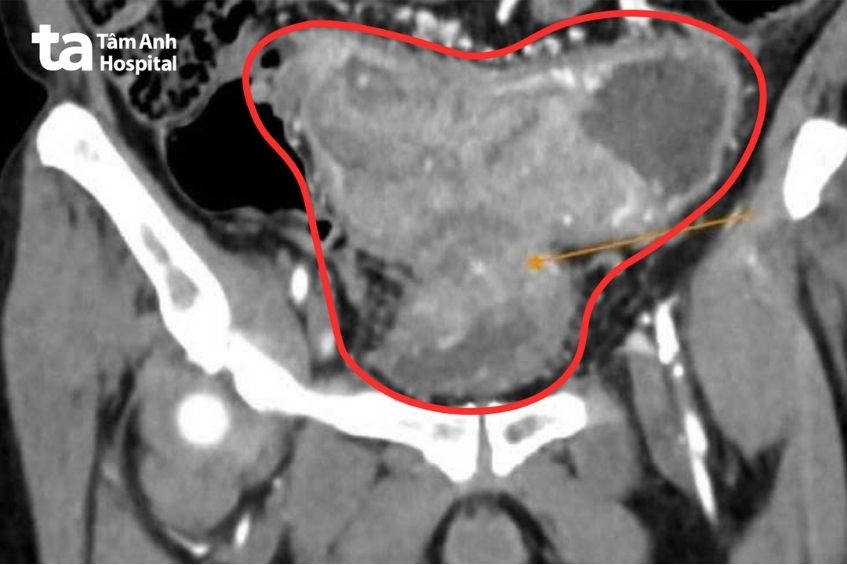

Gia đình đưa ông Minh trở lại Bệnh viện Đa khoa Tâm Anh TP HCM khám. Kết quả chụp CT bụng ghi nhận khối u ác tính gây hẹp hoàn toàn lòng ruột gây dãn ứ phân, xâm lấn gây dày thành bàng quang. Đặc biệt gan có 2 tổn thương do u đại tràng di căn đến.

Bác sĩ CKII Nguyễn Trần Anh Thư, khoa Ung Bướu chẩn đoán ông Minh bị ung thư đại tràng sigma (đoạn ruột cuối cùng, có hình chữ S trước khi nối với trực tràng) giai đoạn 4, xâm lấn bàng quang, di căn gan. “Nếu điều trị ngay ở giai đoạn trước đó, ông Minh chỉ cần phẫu thuật, có thể hóa trị hỗ trợ thêm với liều phù hợp là ổn định sức khỏe” – bác sĩ Anh Thư cho biết.